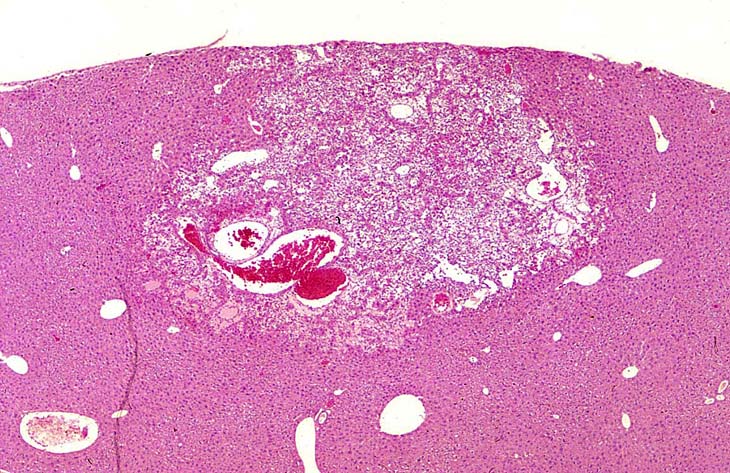

A relative discrete Ito cell tumor is present within this hepatic lobe; a higher magnification shows proliferation of stellate cells within the hepatic sinusoidal spaces.